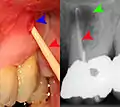

الخطورة

تتراوح خطورة ألم الأسنان من عدم الارتياح الخفيف إلى الألم الشديد، والذي يمكن المعاناة منه إما بشكلٍ مزمن أو على نحوٍ متفرق. قد تتفاقم خطورة هذا الألم بعض الشيء من خلال المضغ أو بسبب درجة الحرارة الساخنة أو الباردة. الفحص الفموي المكتمل باستخدام الأشعة السينية (إكس) يمكنه المساهمة في اكتشاف السبب. قد يعتبر الألم الحاد حالة طوارئ أسنان.